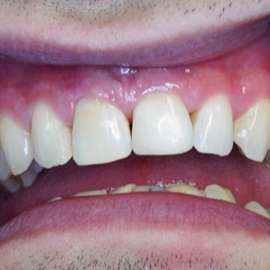

Wybielanie obejmujące pojedyncze zęby jest dość często spotykane. Najczęstszą przyczyną dyskoloracji zęba jest obumarcie miazgi i brak następowego poprawnego leczenia kanałowego, lub leczenie nieprawidłowe. Czasami udaje się przeprowadzić proces wybielania, który jest zadowalający dla pacjenta, a czasami w oparciu o uzyskany wynik można przeprowadzić leczenie protetyczne np. koroną lub licówką całoceramiczną.

Trzeba jednak uważać, ponieważ nieumiejętnie przeprowadzone wybielanie może być przyczyną resorpcji wewnętrznej i może sie skończyć utratą całego zęba...juz wybielonego. Poniżej zdjęcia przed i po leczeniu mikrochirurgicznym resorpcji.